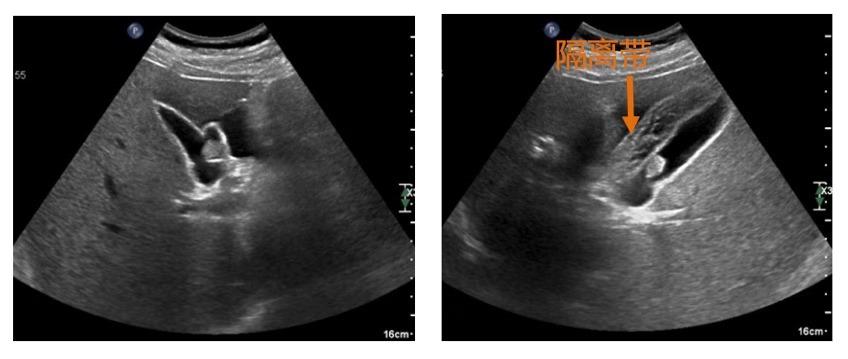

水隔离—注射生理盐水,使胆囊壁浆膜层和黏膜层分离完全,形成厚度>10mm的“隔离带”,使胆囊壁形成显著水肿,增加进针的安全距离。此操作在完成穿刺活检及射频消融中起了决定性的作用!

穿刺—选择最佳穿刺点及进针角度,沿胆囊壁长轴方向进针,尽可能增加路径距离,减小损伤胆囊壁穿孔、造成胆漏的风险。